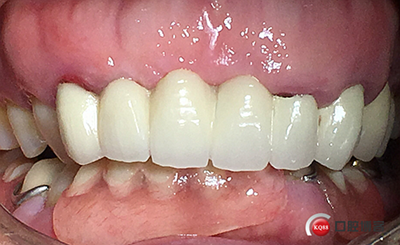

戴牙。

戴牙后半年復(fù)查。